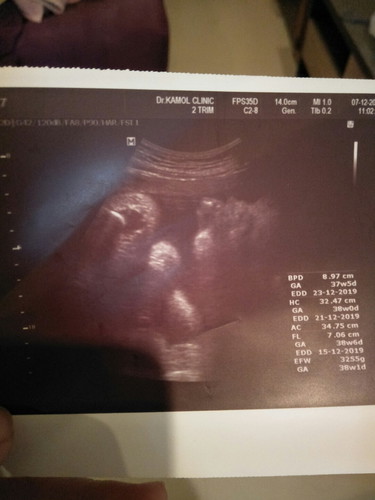

อันนี้ซาวด์ตอน38wพอดี น้องหนัก3255gได้ลูกสาวผ่าวันศุกร์นี้แล้วคะ แม่ๆทีมธันวาแอบแตกกันไปหรือยังคะ??